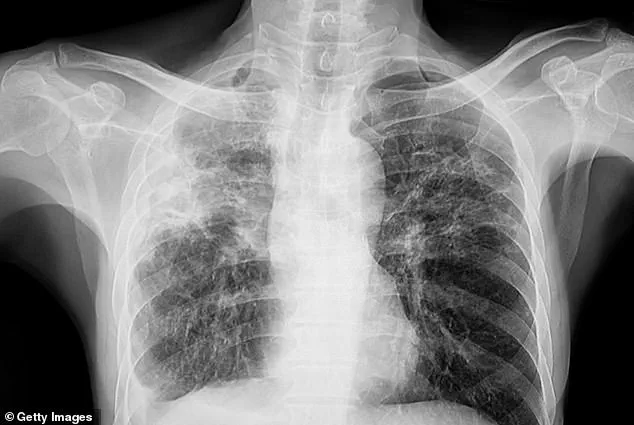

The cases, all diagnosed with active tuberculosis—where the bacteria is multiplying in the lungs—have sparked immediate public health efforts to trace and isolate close contacts.

If left untreated, the disease can progress to severe breathing difficulties, extensive lung damage, and the spread of infection to other organs such as the liver or spine, causing localized pain.

In the most advanced stages, respiratory failure due to lung damage can be fatal, as the body is no longer able to take in sufficient oxygen.